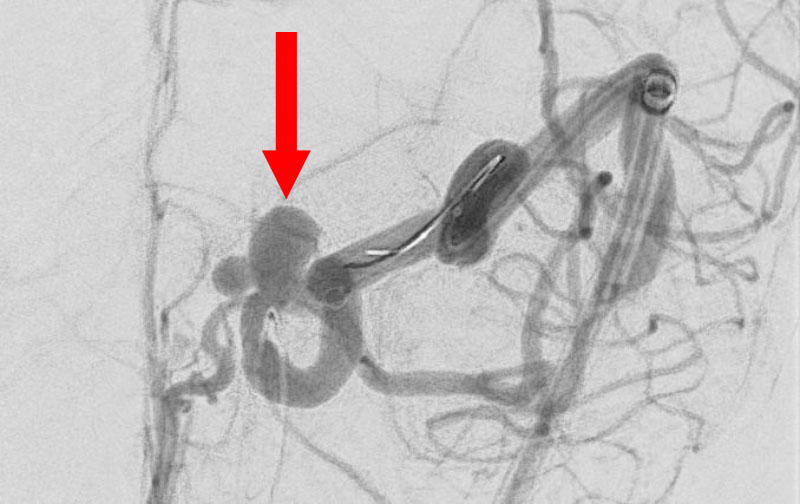

No.1593 手術後